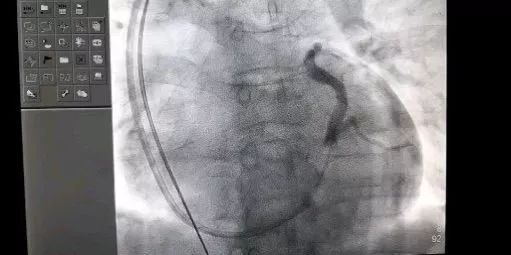

术中冠状窦

第一准确找到冠状静脉窦(CS):CS位于心脏的后部,绕左心房与左心室之间的冠状沟而行,开口似孔状,心衰患者的心脏扩大,CS位置偏离了正常解剖位置,想要准确找到CS开口非常困难,考验术者对心脏解剖的熟知程度及电生理、电极导管的操作熟练程度及控制能力。术者刘东亮教授独立完成射频消融近二千余例对电生理的各种电极导管操作非常熟练,非常顺利的找到CS开口,并把指引导管一次到位。

第二步选择一个理想的靶血管:根据冠状静脉窦造影显示该患者的,侧静脉是理想的靶血管,中远端在左室侧后壁,但开口角度刁且弯曲重,术者熟练的应用冠脉PTCA导丝的掌控技术,运用分支递送导管,超选侧静脉将PTCA用的sion blue导丝准确的植入靶血管。